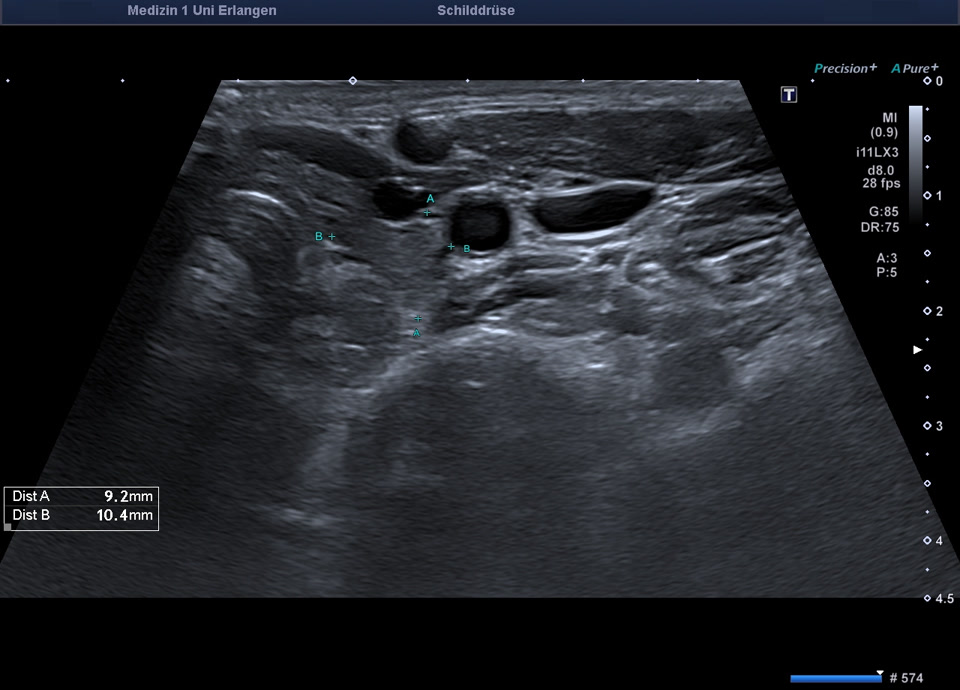

36-year-old patient with tremor, tachycardia, exophthalmos, and weight loss. Thyroid ultrasound shows bilaterally hypoechoic, inhomogeneous parenchyma with a total volume of 20.5 ml. Color Doppler sonography shows hypervascularization. Laboratory results: basal TSH decreased, T3/fT4 elevated, TRAK positive, consistent with Graves’ disease. Symptoms resolved under treatment with thiamazole and propranolol. At follow-up two years later, sonography showed a hyperechoic minimally inhomogeneous parenchyma with normal volume (15 ml).